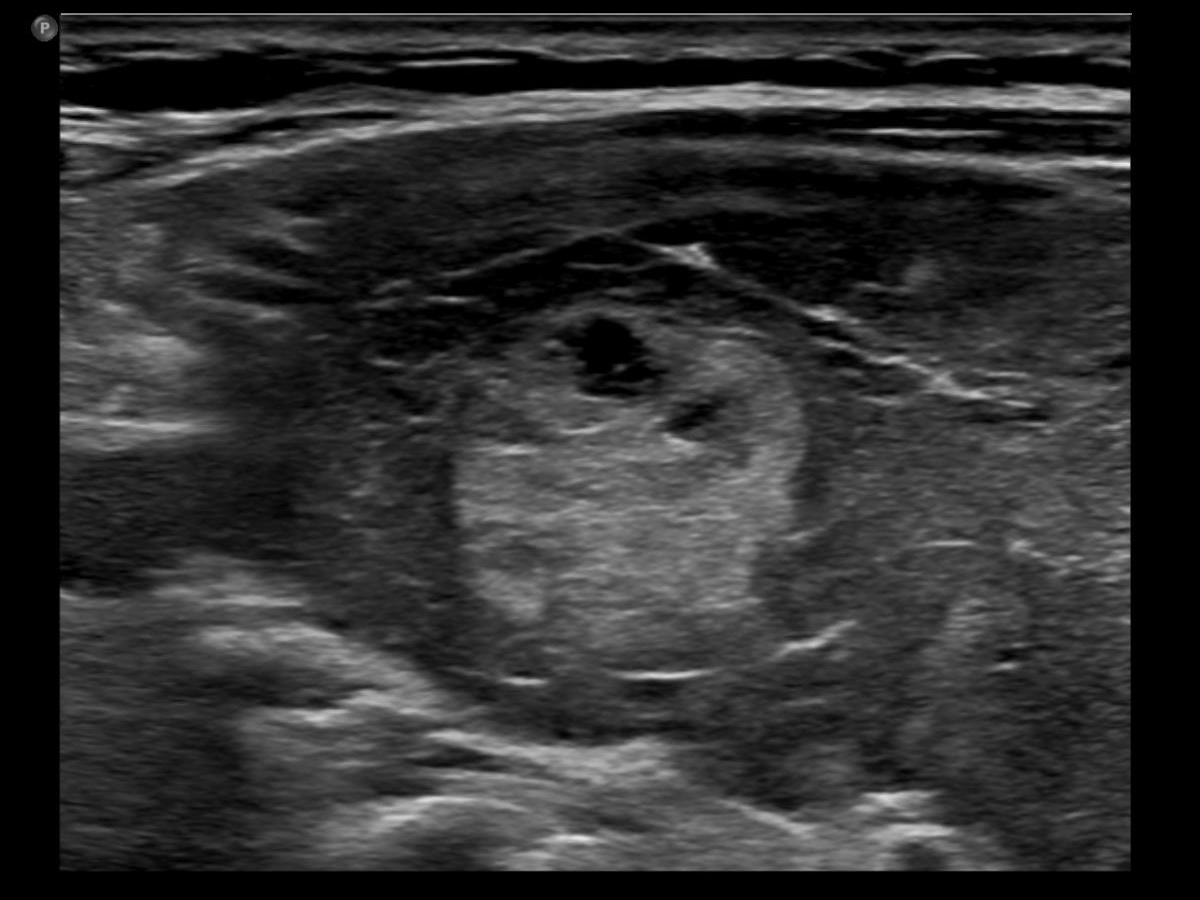

Three years after the first examination (third row of images):

Clinical presentation. The patient has ceased the thyrostatic therapy for six months. Recently, she noticed again complaints suggesting hyperthyroidism.

Palpation: unchanged.

Results of blood tests: hyperthyroidism (TSH undetectable, FT4 39.1 pM/L).

Ultrasonography. There were two changes compared with the previous examination. The thyroid has become echonormal while the lesion in the right lobe has become again hypoechoic.Suggestion: daily 20 mg methimazole. Radioiodine therapy when the FT4 level will become normal.